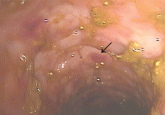

ArticleCytomegalovirus colitisAuthor:Abdulrahman Abdulbaki, MDPublish date: January 1, 2012Cytomegalovirus colitis is common in patients on immunosuppressive therapy for inflammatory bowel disease.Read More